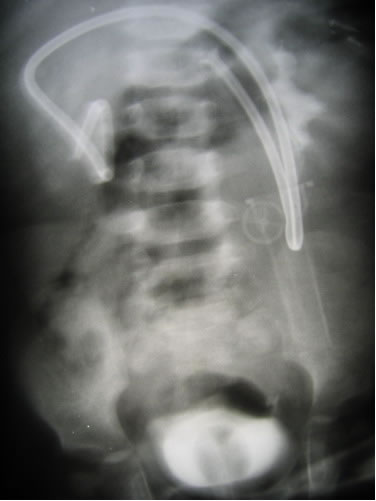

Экскреторная урография

Выполнено оперативное вмешательство:

Уретероцистоанастомоз справа по экстравезикальной

методике